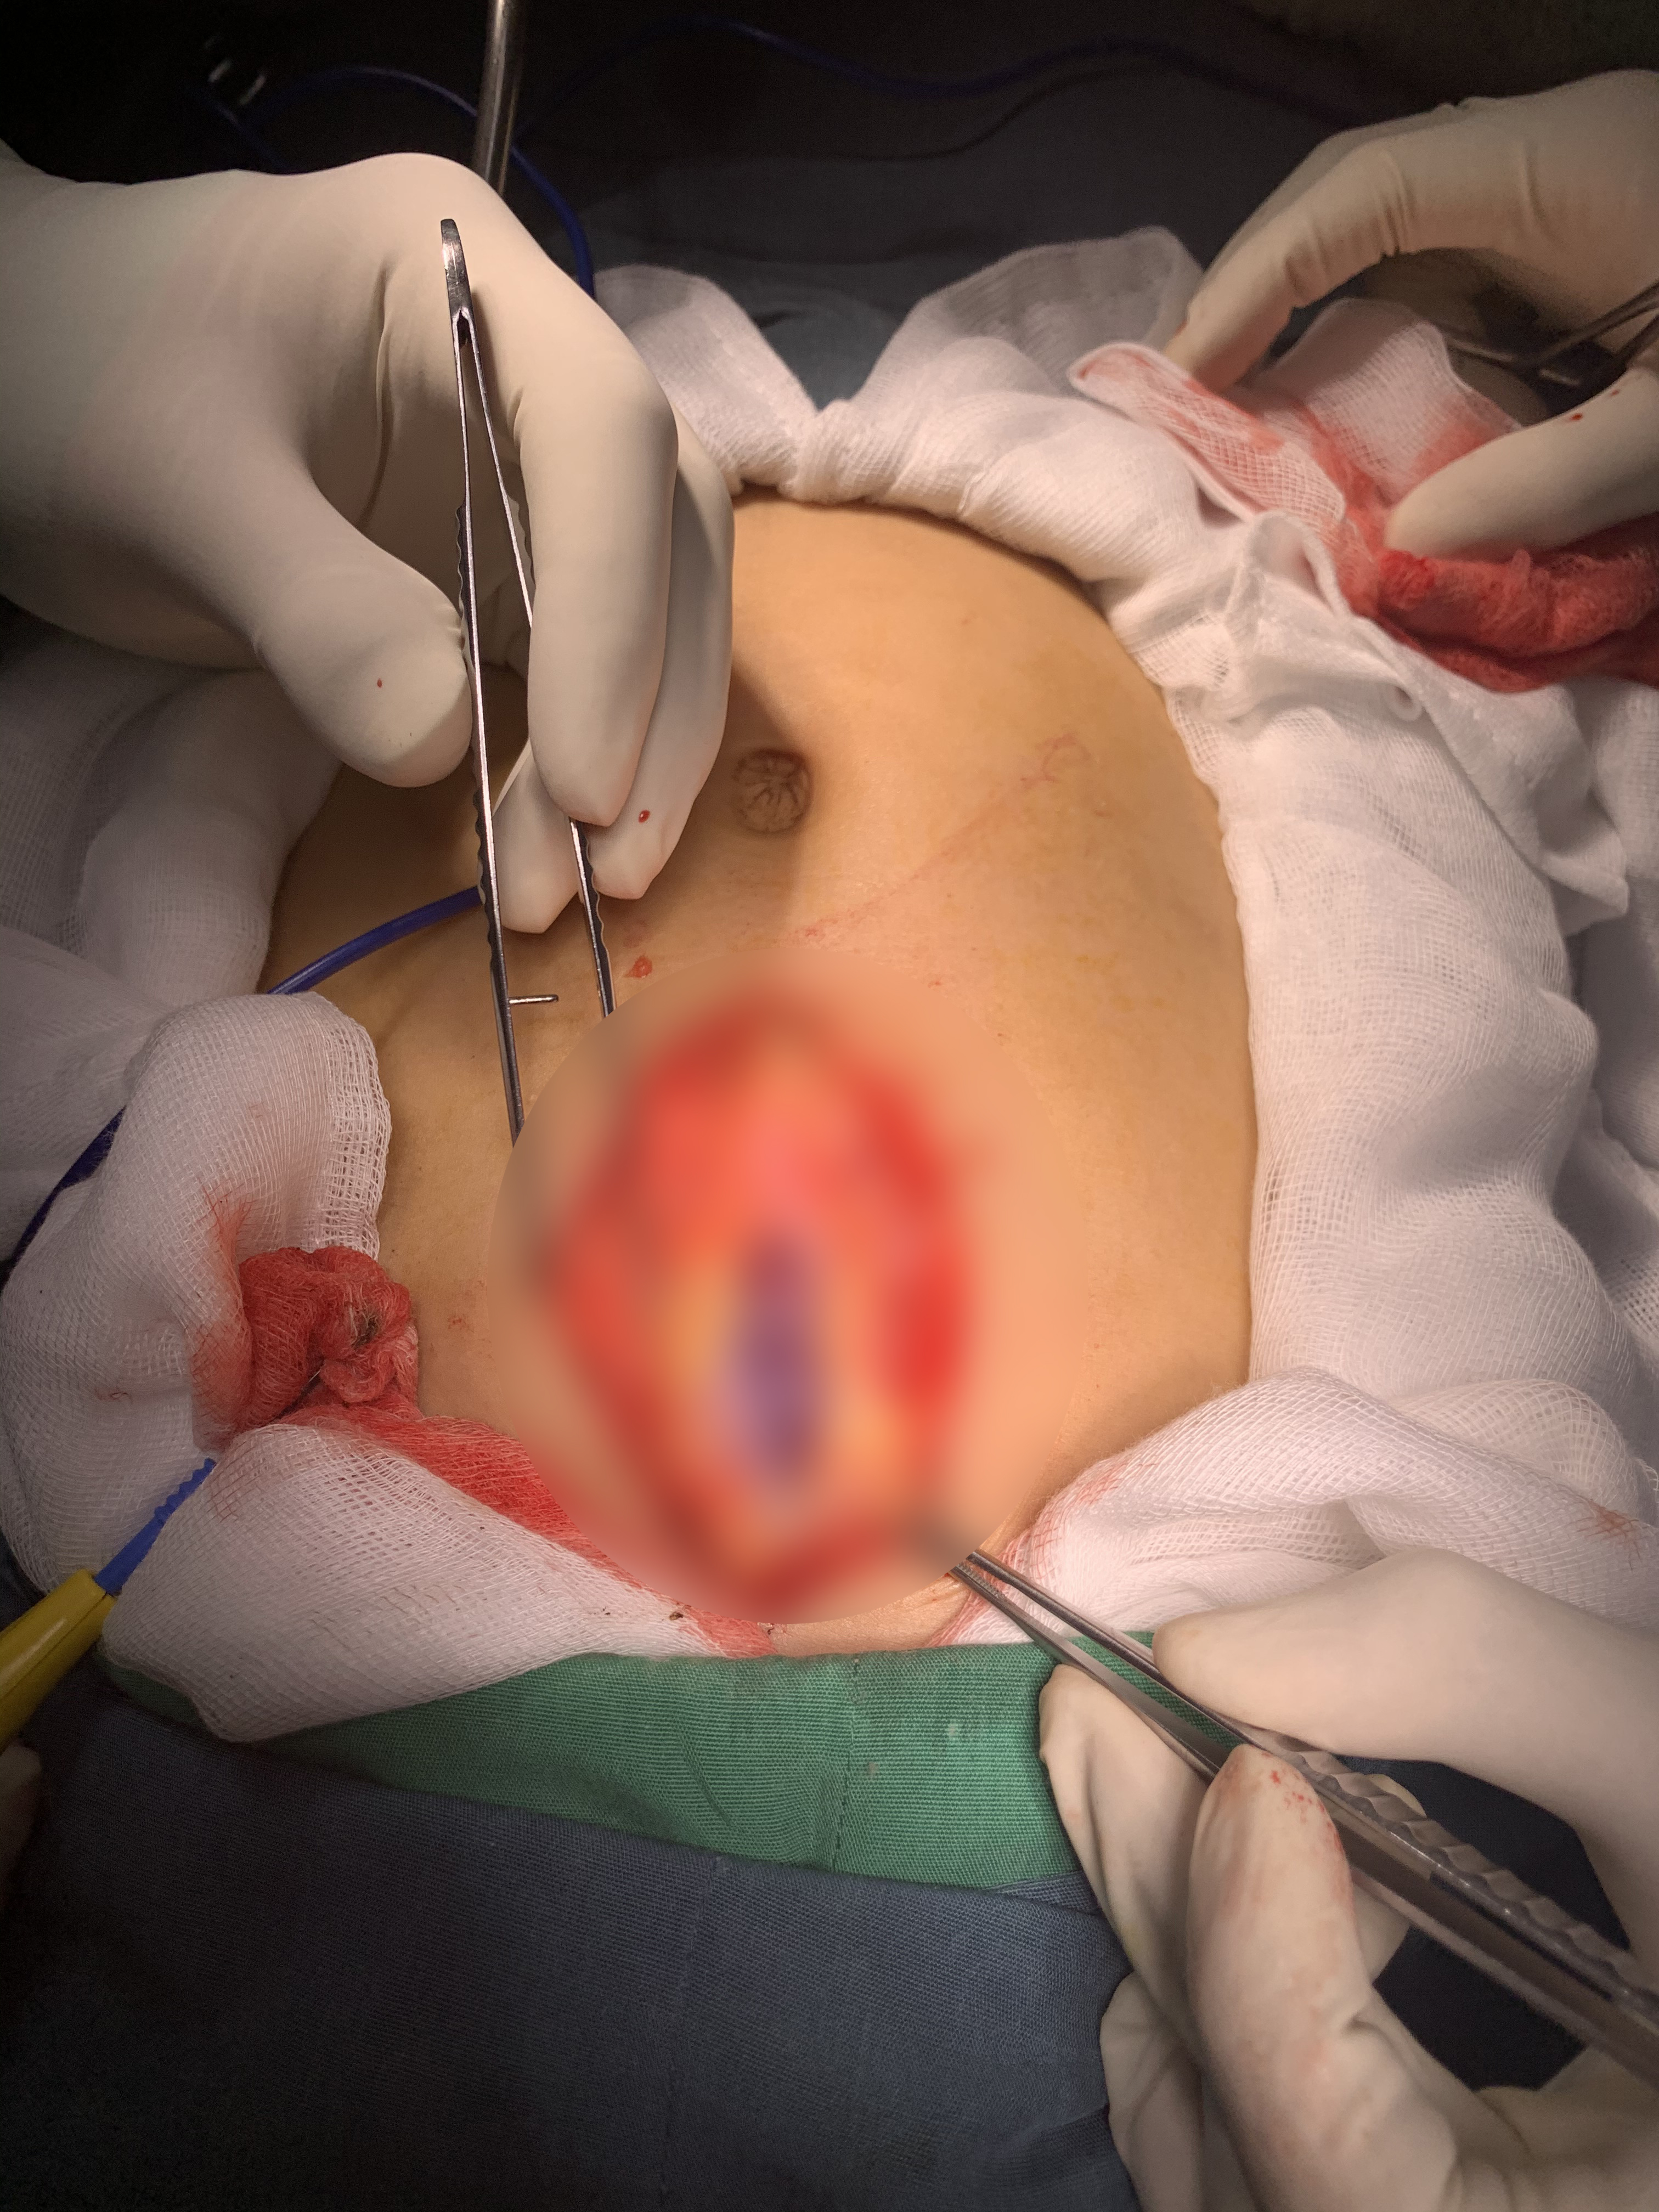

Áp lực máu làm phồng phúc mạc.

Khi nhập viện bé T. tỉnh, kêu đau nhiều vùng hạ sườn trái, khát nước và có vẻ hoảng hốt. Bụng không chướng, vết bầm vùng hạ sườn trái, ấn đau vùng hạ sườn trái, được truyền dịch, giảm đau .

Siêu âm lúc nhập viện kết quả chấn thương lách. Sau 2 giờ, bé cảm giác đau nhiều hơn, diễn tiến nặng. Bé được truyền dịch và chống sốc, truyền máu,ekip trực nhân thấy cần phải tiến hành phẫu thuật.